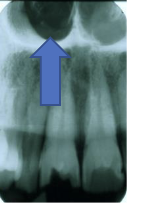

Nasal Cavity/Fossa

large radiolucent area above the max incisors (aka nasal fossa)

(radiolucent)

Maxillary Sinus

radiolucent area located above the apices of the premolar/molar areas in maxilla